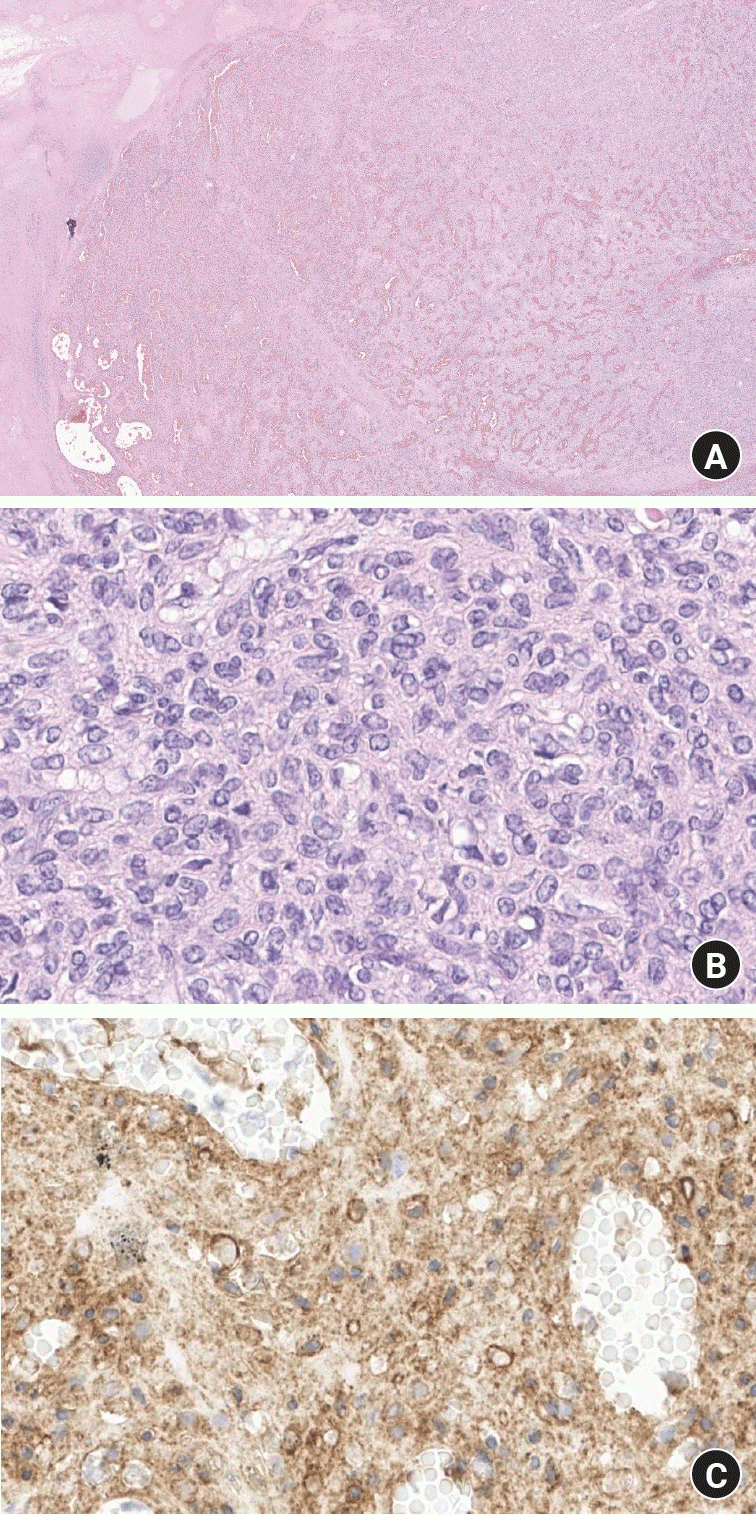

Histopathological examination of the excised specimen revealed several key features indicative of a complex vascular lesion, possibly KHE. The examination was conducted on multiple sections, stained with hematoxylin and eosin as well as immunohistochemical staining for CD34. At lower magnification, the specimen exhibited a multinodular mass with areas resembling capillary hemangiomas (Fig. 7A). The architecture was lobulated with intervening stromal fibrosis and occasional lymphoid aggregates, supporting the differential diagnosis of KHE with possible features of Kasabach-Merritt syndrome. Microscopic evaluation showed tumor cells with mild to moderate nuclear pleomorphism, which is a hallmark of cellular atypia (Fig. 7B). Mitotic figures were sparse, suggesting a low mitotic rate which is typical for KHE rather than more aggressive vascular tumors. And finally, the CD34 staining demonstrated diffuse cytoplasmic positivity in tumor cells, indicating a rich vascular component and endothelial differentiation (Fig. 7C). This finding supports the vascular nature of the tumor, consistent with the characteristics of KHE.

Fig. 7.

Histopathological features of kaposiform hemangioendothelioma. (A) Overview showing a capillary hemangioma-like multinodular mass. Hematoxylin and eosin (H&E) stain, ×15. (B) Higher magnification displaying mild to moderate nuclear pleomorphism with rare mitotic figures. H&E stain, ×400. (C) Immunohistochemical staining showing diffuse cytoplasmic positivity, indicating vascular endothelial differentiation in tumor cells. CD34 stain, ×400.